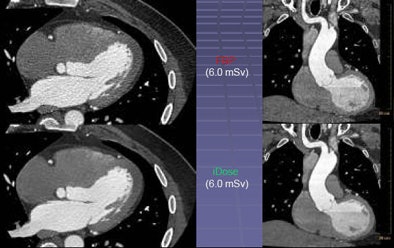

In contrast, the iDose algorithm (Philips Healthcare, Andover, MA) that Mendel described in his ISCT talk uses an iterative method designed to reproduce the look of full-dose filtered back projection (FBP) at a much lower dose using an iterative method. The goal is to allow use of a higher percentage of iterative reconstruction while maintaining a clinically acceptable image.

First, the projection data itself are denoised with the application of a Poisson denoising algorithm. Then in the pixel space, iDose compares the image to a noiseless ideal anatomical model, enabling noise reduction with an appearance that is very similar to the full-dose image and does not shift the noise spectrum significantly, Mendel said.

"So even at 80% dose reduction, the images are virtually identical" to a full-dose image, even when the images are rendered, he said. In contrast, the first-generation systems show major shifts in the noise spectrum, sharpening edges and blurring other structures compared to standard images.

The key aspect of iDose is that it maintains the noise power spectrum (thus the appearance) of a full-dose image while utilizing high levels of dose reduction, Mendel said.